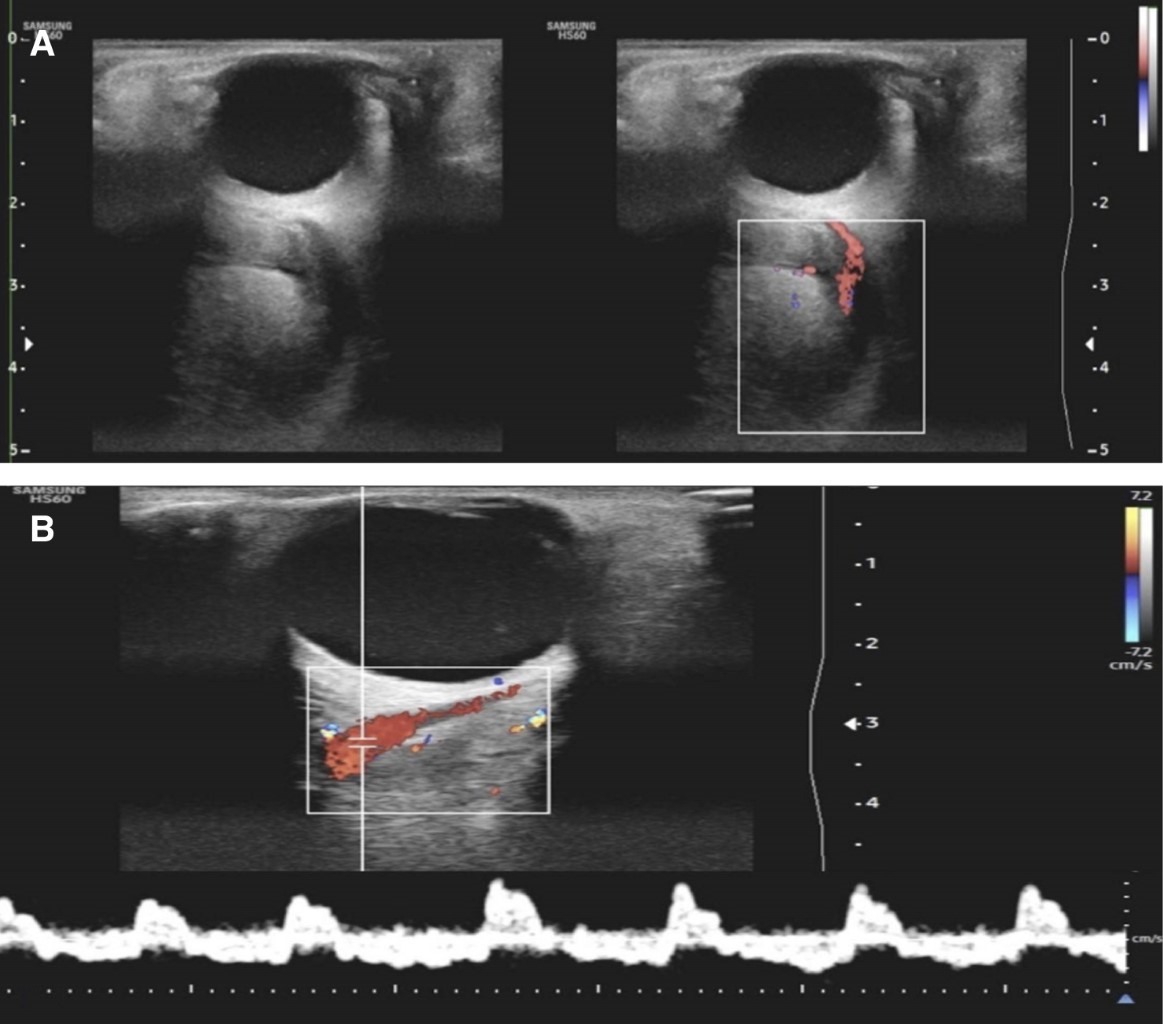

Debido a los hallazgos correspondientes, se sugirió un estudio diagnóstico confirmatorio de angiografía por sustracción digital que lamentablemente fue rechazada por el paciente. Se realizó una ecografía complementaria que mostró una vena oftálmica izquierda con la presencia de un componente hipoecoico intraluminal, causante de obstrucción y flujo filiforme, también se observa orientación bidireccional del flujo con Doppler espectral, lo cual es correspondiente a un patrón de flujo de fístula arteriovenosa (Figura 3).

Figura 3